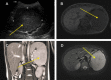

Hamartomas are extremely rare splenic benign tumours in children. We present two cases, both in boys (6 and 8 years old), with left upper quadrant abdominal pain that were otherwise asymptomatic. Both patients showed a splenic mass on preoperative ultrasonography and magnetic resonance imaging (MRI). One patient had a focal splenic mass that was identified preoperatively with contrasted computed tomography (CT) scans. Both patients underwent a total splenectomy. Although multi-modality imaging findings were described preoperatively, the final diagnosis in each case was splenic hamartoma based on histology and immunohistochemistry. The postoperative courses were uneventful.